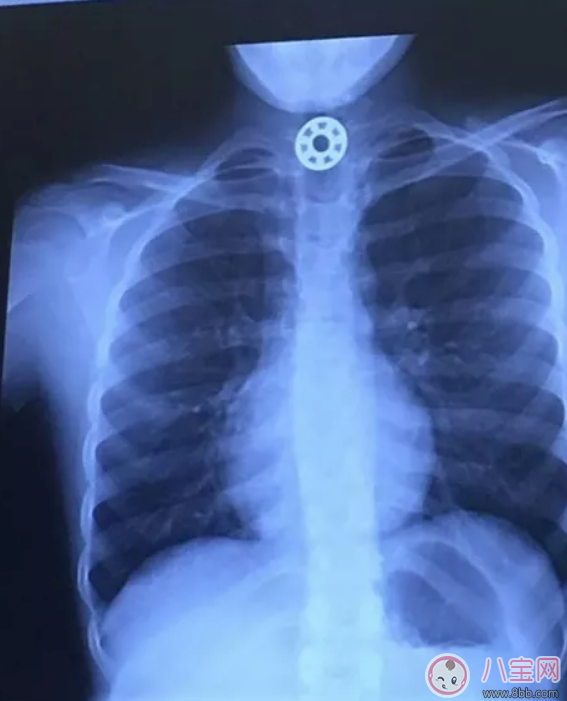

2017年5月,美國德州一位母親Kelly Rose Joniec開車載著女兒游完泳回家時,突然聽到后座傳來干嘔聲,發現10歲女兒Britton 滿臉脹紅還不停流口水,有窒息的情況。

Britton指著喉嚨發出痛苦的聲音,說自己吞下了指尖陀螺的金屬零件。緊張的Kelly 當下先用了哈姆立克急救法,但是沒有效果,趕緊將女兒送醫。

醫生檢查發現,一個小小的金屬片卡在食道內,試了好幾次都無法順利取出。只好安排手術,用內窺鏡協助終于把這個造成女孩窒息的東西拿出來。這個金屬零件比一枚25美分硬幣還要小。